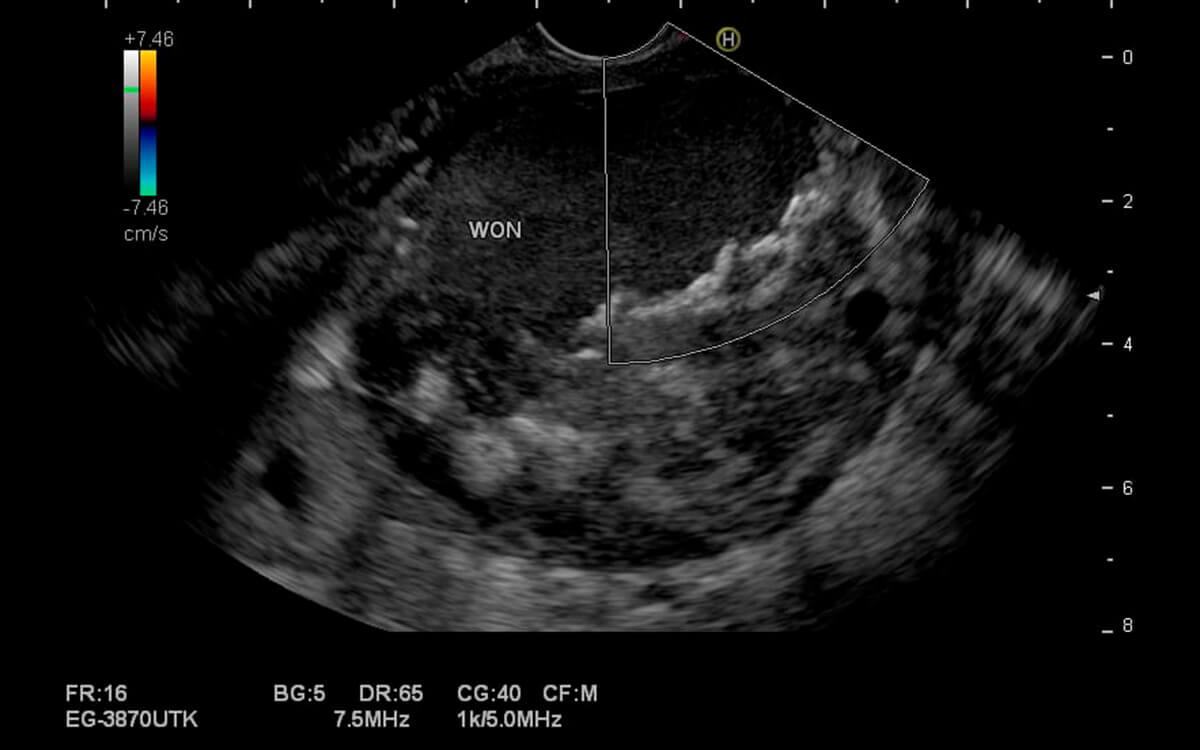

A Ecoendoscopia Gastrointestinal , é um exame diagnóstico e potencialmente terapêutico do trato digestivo alto e baixo. O médico endoscopista pode analisar o esôfago, estômago, duodeno, pâncreas, vias biliares, vesícula biliar, fígado, intestino (cólon) e reto com um ultrassom, através de acesso por endoscopia (ecoendoscopia alta) ou colonoscopia (ecoendoscopia baixa).

O Dr. Hugo Guedes, médico especialista em Ecoendoscopia Gastrointestinal pela USP e do Hospital Sírio Libanês, explica que "a ecoendoscopia possibilita examinar camadas mais profundas dos órgãos digestivos, que não poderiam ser avaliadas apenas pela endoscopia comum, pois esta permite apenas a visualização superficial de suas paredes internas".

Ecoendoscopia Gastrointestinal faz o exame ultrassonográfico do aparelho digestivo, além de permitir a realização de punção por agulha diretamente desses órgãos (ecoendoscopia com biópsia). Dessa forma, podemos analisar diversas doenças do trato digestivo, como: